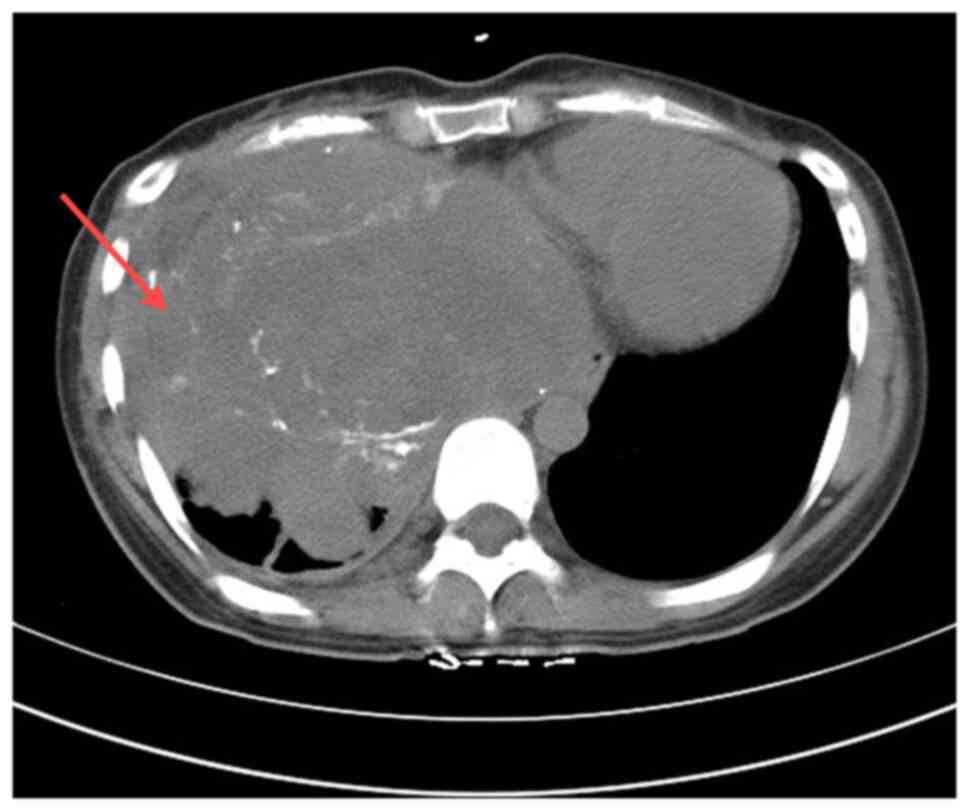

Figure 1.

Enhanced computed tomography image showing an irregular mass (red arrow) in the right thorax.

A 24-year-old female patient was admitted to the Affiliated Hospital of Zunyi Medical University (Zunyi, China) in November 2012 due to right chest pain for 10 months and aggravation for 4 months. The patient initially experienced dull pain in the right side of the chest without any apparent cause. The patient had no symptoms, such as a cough, phlegm, cold, fever, abdominal pain or distension. At 10 months prior to admission, the patient was treated at Affiliated Hospital of Guiyang Medical College (Guiyang, China) for dull right-sided chest pain. A chest and abdominal computed tomography (CT) scan revealed a large space in the right upper diaphragm and right pleural effusion. Despite 6 months of treatment for right-sided tuberculous pleurisy, the symptoms persisted, and a mass puncture performed 4 months prior to the current admission identified a spindle cell tumor. In the last 3 months, the patient's chest pain on the right side continued to worsen, prompting a transfer to the Affiliated Hospital of Zunyi Medical University for further treatment. The patient was admitted with a diagnosis of a right thoracic tumor. Upon physical examination, the following findings were noted: Decreased respiratory motion of the right lung, pain induced by light pressure on the right chest wall, a solid sound on percussion of the right lung and a leftward shift of the relative border of cardiac dullness. Laboratory tests for tumor markers and biochemical indicators were normal. A chest CT scan showed irregular masses in the right lower thorax, the right middle mediastinum and the diaphragm area, with unclear borders and uneven density. CT values ranged from 25–65 Hounsfield units, with a maximum cross-sectional area of ~173×140 mm. Multiple nodular and small dot-like high-density shadows were observed. Enhancement scans indicated heterogeneous enhancement, significant compression and deformation of the right inferior pulmonary vein and right atrium, a poor display of the right atrium, and a leftward shift of the mediastinum and heart. No adjacent bone destruction was observed (Fig. 1). The patient had no specific past medical or family history. The patient underwent a thoracotomy for a suspected primary thoracic tumor. Intraoperatively, yellowish effusion was noted in the right thorax, and the tumor occupied approximately three-quarters of the right thorax, displaying a large lobulated morphology. The tumor exhibited aggressive growth, invading the diaphragm, lower lung, mediastinum and part of the chest wall, with an incomplete capsule. The tumor protruded downward into the abdominal cavity, but did not invade the liver and heart, with a clear demarcation between the tumor and the pericardium.